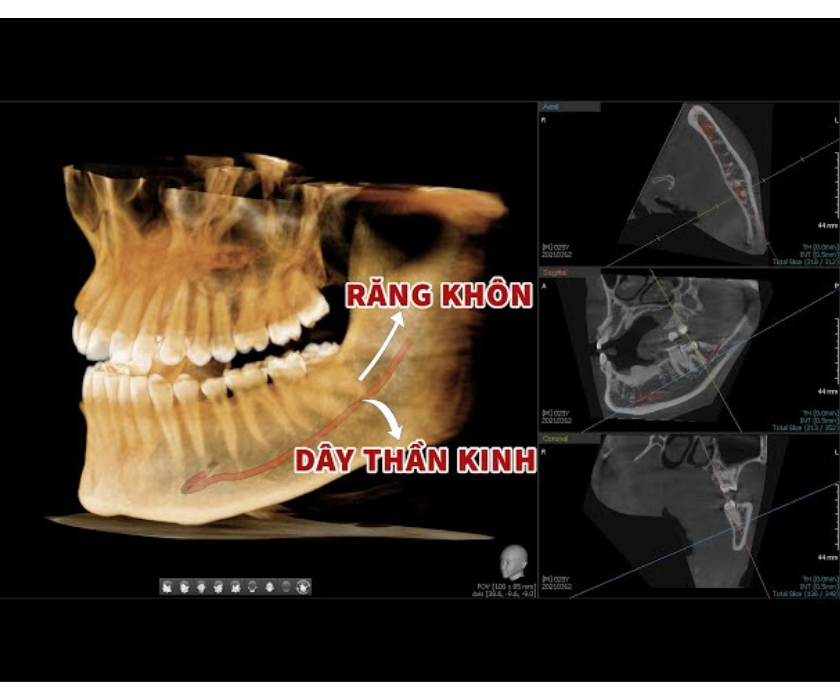

- Gần hệ thống dây thần kinh quan trọng:

Chân răng khôn hàm dưới thường nằm gần hoặc sát với ống dây thần kinh hàm dưới – dây thần kinh chi phối cảm giác cho vùng môi, cằm, và nướu hàm dưới. Nếu nhổ không đúng kỹ thuật hoặc có thao tác mạnh tay, bệnh nhân có thể bị tê môi, mất cảm giác tạm thời hoặc vĩnh viễn. - Gây khó khăn trong gây tê và thao tác phẫu thuật:

2. Tổn thương dây thần kinh

Nhổ răng khôn hàm dưới dễ biến chứng tổn thương dây thần kinh

Dây thần kinh răng dưới và thần kinh lưỡi nằm gần chân răng khôn hàm dưới. Nếu không được chẩn đoán chính xác bằng phim CT 3D hoặc tay nghề bác sĩ không đủ kinh nghiệm, việc nhổ răng có thể làm tổn thương dây thần kinh.

Hậu quả là người bệnh có thể bị tê môi, tê lưỡi, mất cảm giác vùng cằm – lưỡi, thậm chí kéo dài hàng tháng hoặc vĩnh viễn trong một số trường hợp hiếm gặp.

- Chụp phim CT Cone Beam 3D trước nhổ

Trước khi tiến hành nhổ răng khôn, bác sĩ sẽ chỉ định chụp CT Cone Beam – một loại phim 3D cho phép nhìn rõ cấu trúc xương hàm, vị trí chân răng, hướng mọc, và khoảng cách đến các dây thần kinh, xoang hàm. Nhờ hình ảnh này, bác sĩ có thể lên kế hoạch phẫu thuật chính xác, hạn chế tối đa nguy cơ sang chấn không đáng có.

Đặc biệt với răng khôn hàm dưới gần dây thần kinh, CT 3D là yếu tố không thể thiếu để đảm bảo an toàn tuyệt đối.